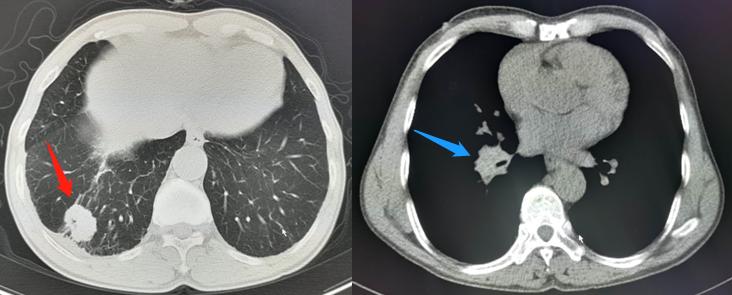

一位62岁病人,咳嗽2个月,没有其他不舒服,以往有慢性支气管炎、肺气肿病史多年。

红箭头为小肺癌,周围型;蓝箭头为肺门淋巴结转移

结果,CT发现右下肺2.8厘米小肺癌,很小,但已经发生肺门、纵隔淋巴结多发转移了……

做了经皮肺穿刺,确诊为低分化腺癌,癌细胞呈实性生长,目前正在等待医院的基因检测结果……